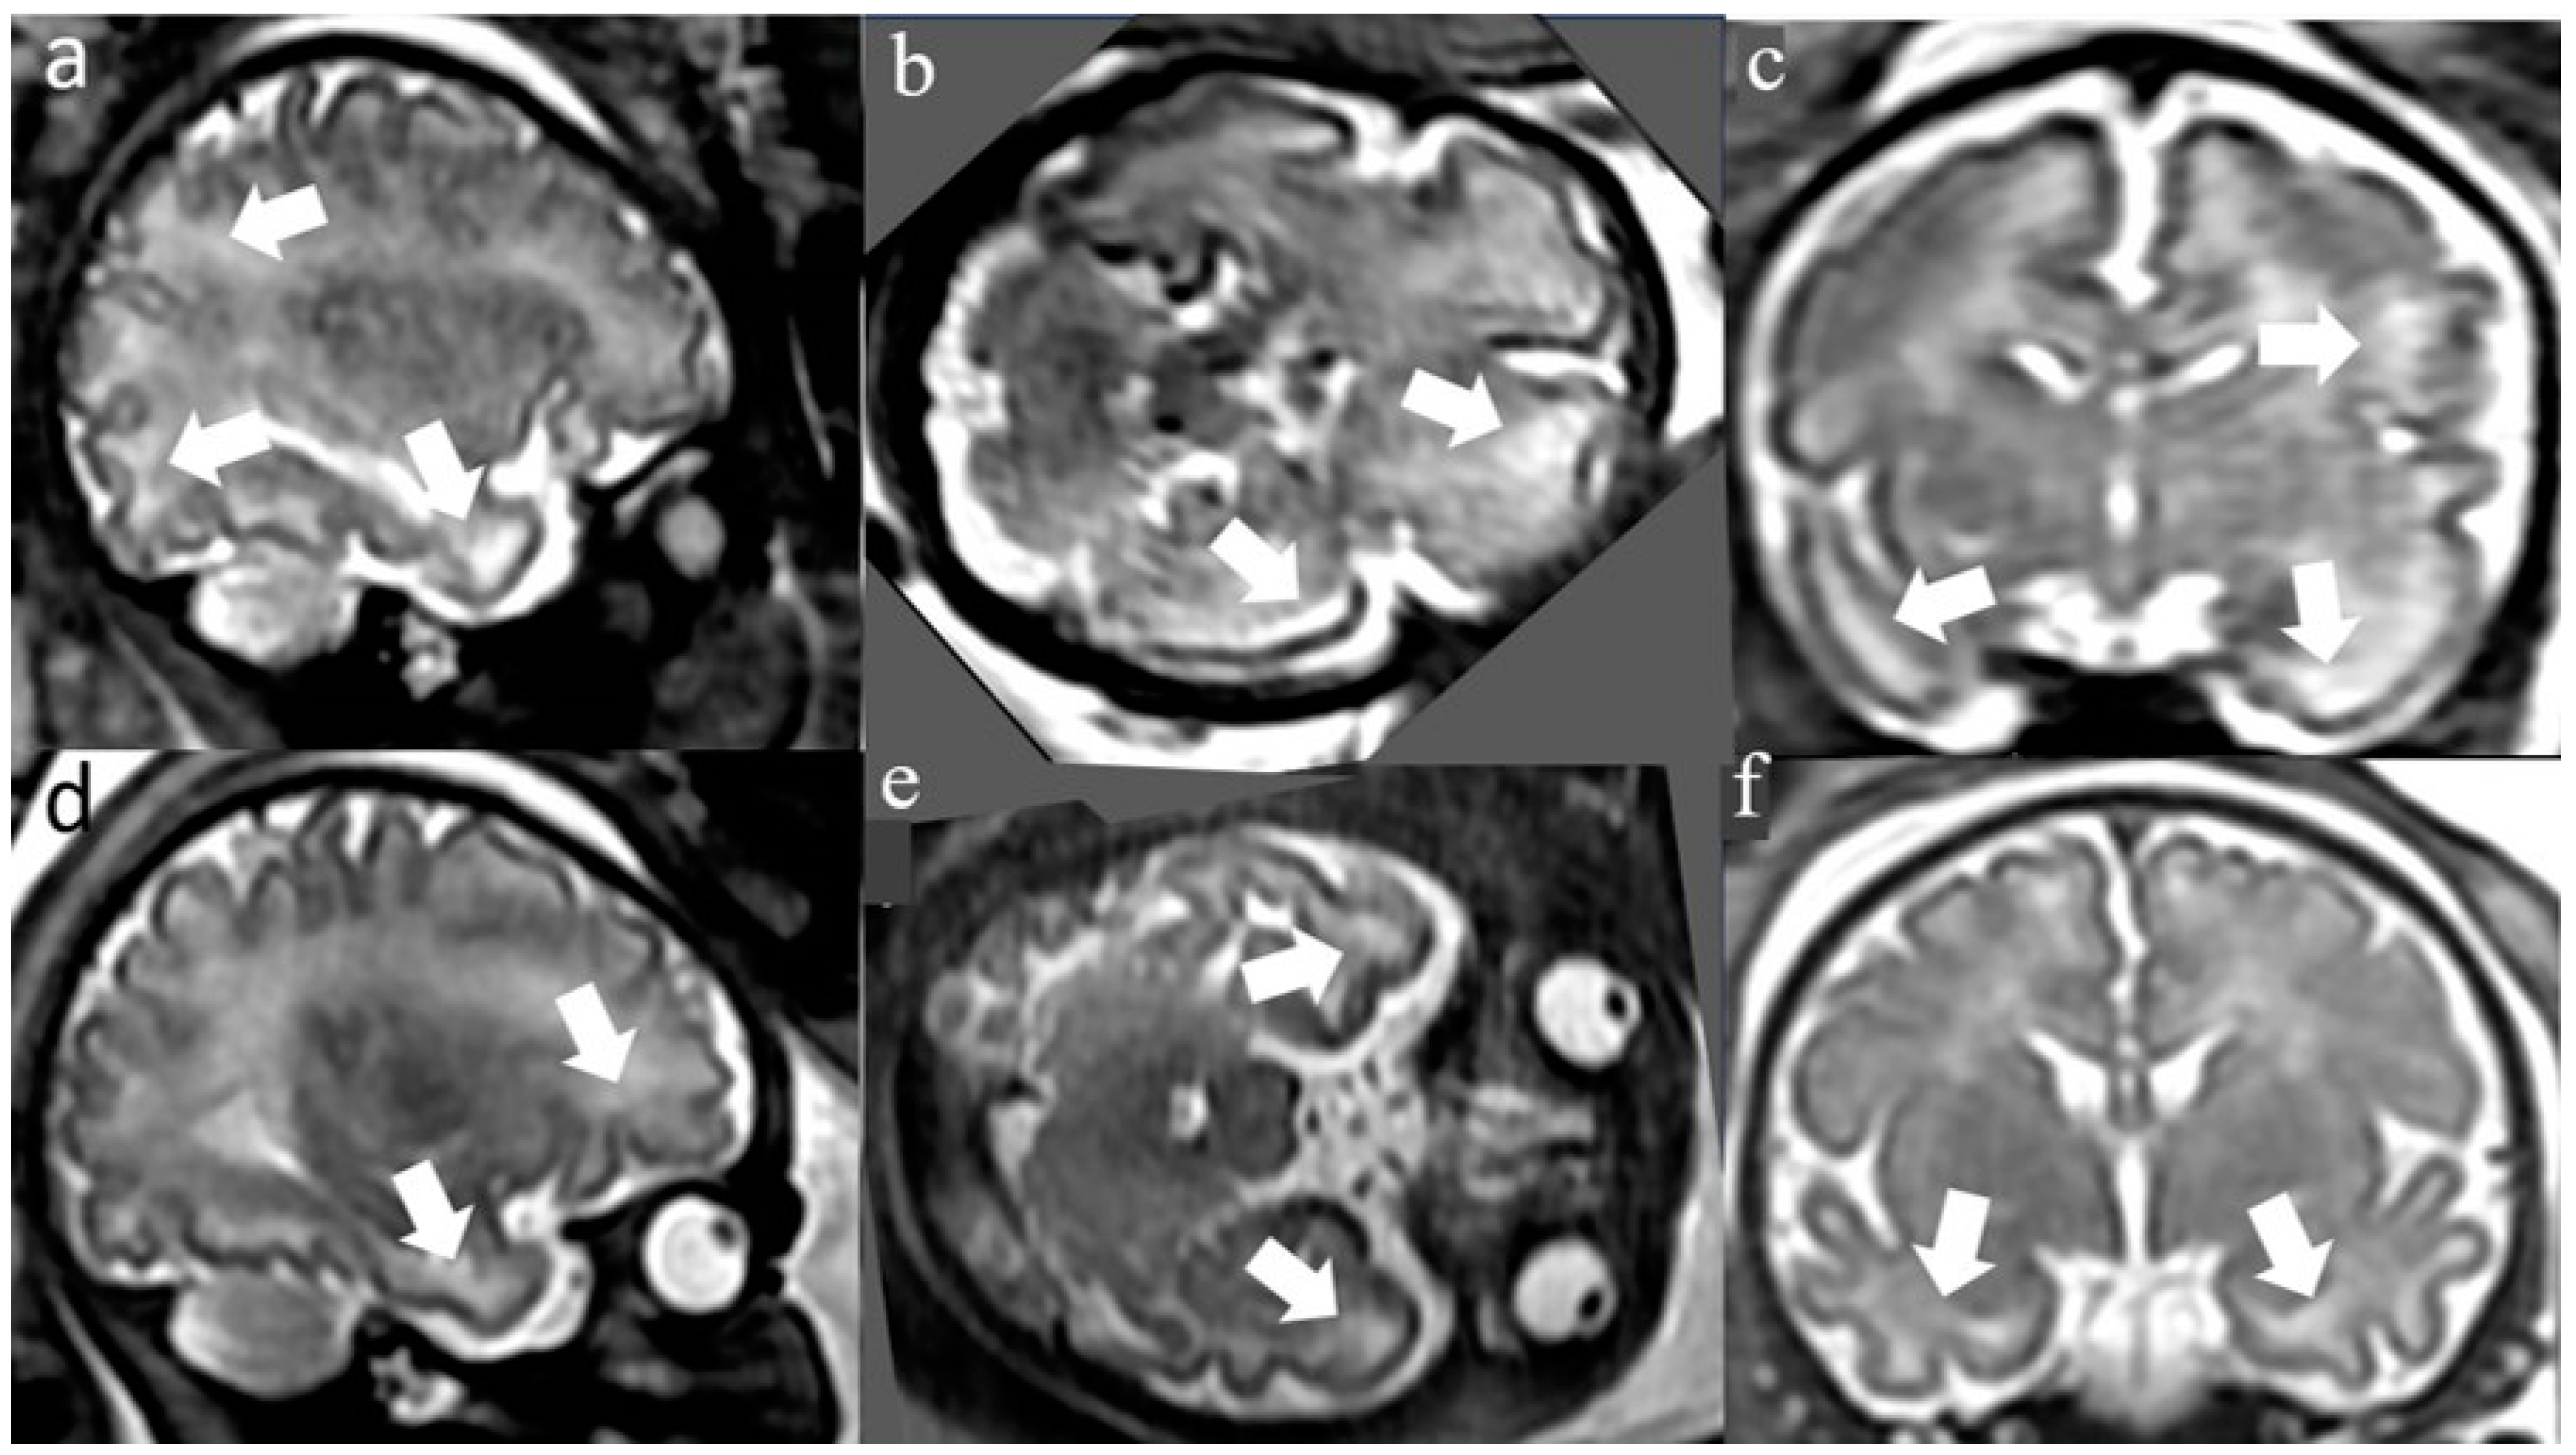

2.3. White Matter T2 Hyper-Intense Signal (WMHS)